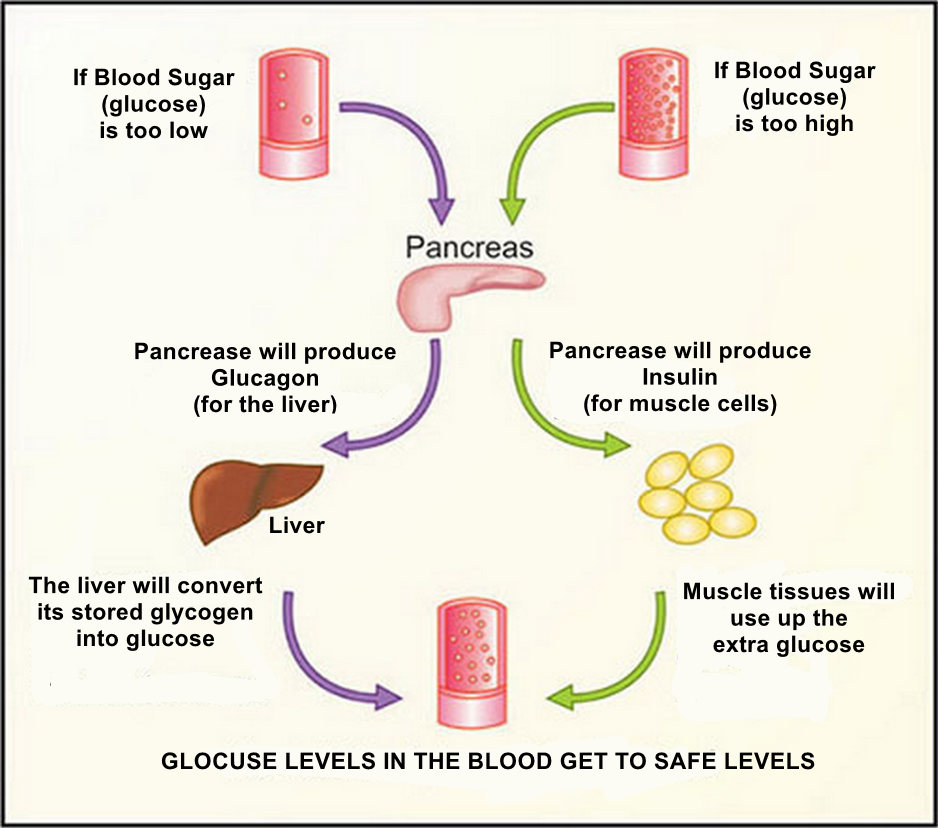

Pancreas #

The pancreas is a large gland located behind your stomach. It produces hormones that control blood sugar levels.

Main Hormones: Insulin and Glucagon

Main Function: Controls blood glucose (sugar) levels

Pancreatic Hormones:

- Insulin: Lowers blood glucose levels by helping cells absorb glucose from the blood

- Glucagon: Raises blood glucose levels by causing the liver to convert its stored Glucagon into Glocose and release it into the blood